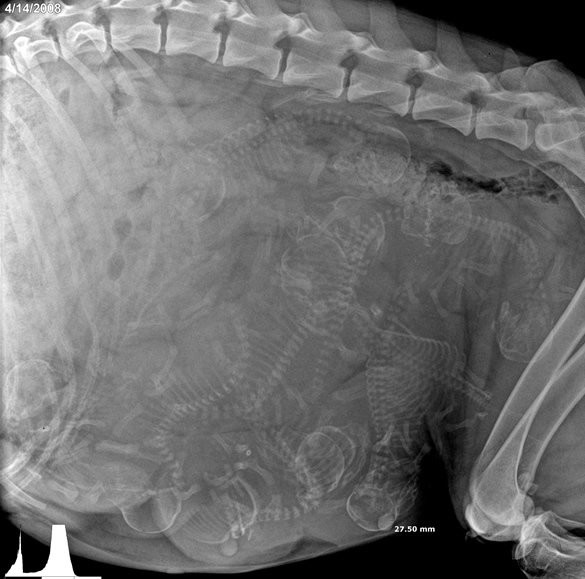

Хээл авсан амьтадын хэвлийн рентген зураг ингэж харагддаг. Хэдий итгэмээргүй ч ийм л байна.